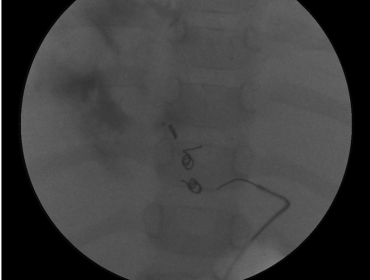

Mesenteric Bypass

Hepatic Aneurysm Coiling